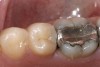

Replacement of existing restorations is responsible for 75% of all operative dentistry.15,19 The reasons for placement and replacement of restorations of direct restorative materials include: primary caries (Figure 1 and Figure 2); recurrent caries (Figure 3); poor margins (Figure 4 and Figure 5); restoration fracture (Figure 6 and Figure 7); tooth fracture (Figure 8); esthetics (Figure 9); non-carious tooth structure lost (attrition, abrasion, abfraction, erosion) (Figure 10); and pain/sensitivity.

Figure 4  Defective margins. Mandibular first molar with an amalgam restoration with defective margins.

Figure 4